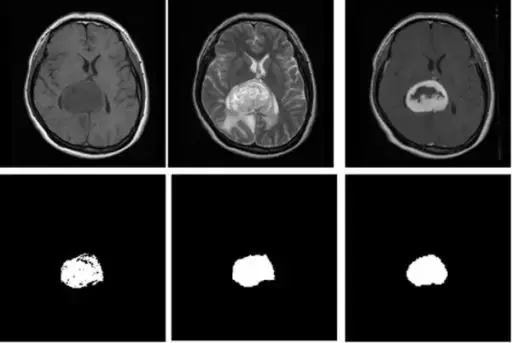

脑部肿瘤分割示例

代码地址:https://github.com/Issam28/Brain-tumor-segmentation

论文题目:《Deep Convolutional Neural Networks Using U-Net for Automatic Brain Tumor Segmentation in Multimodal MRI Volumes》